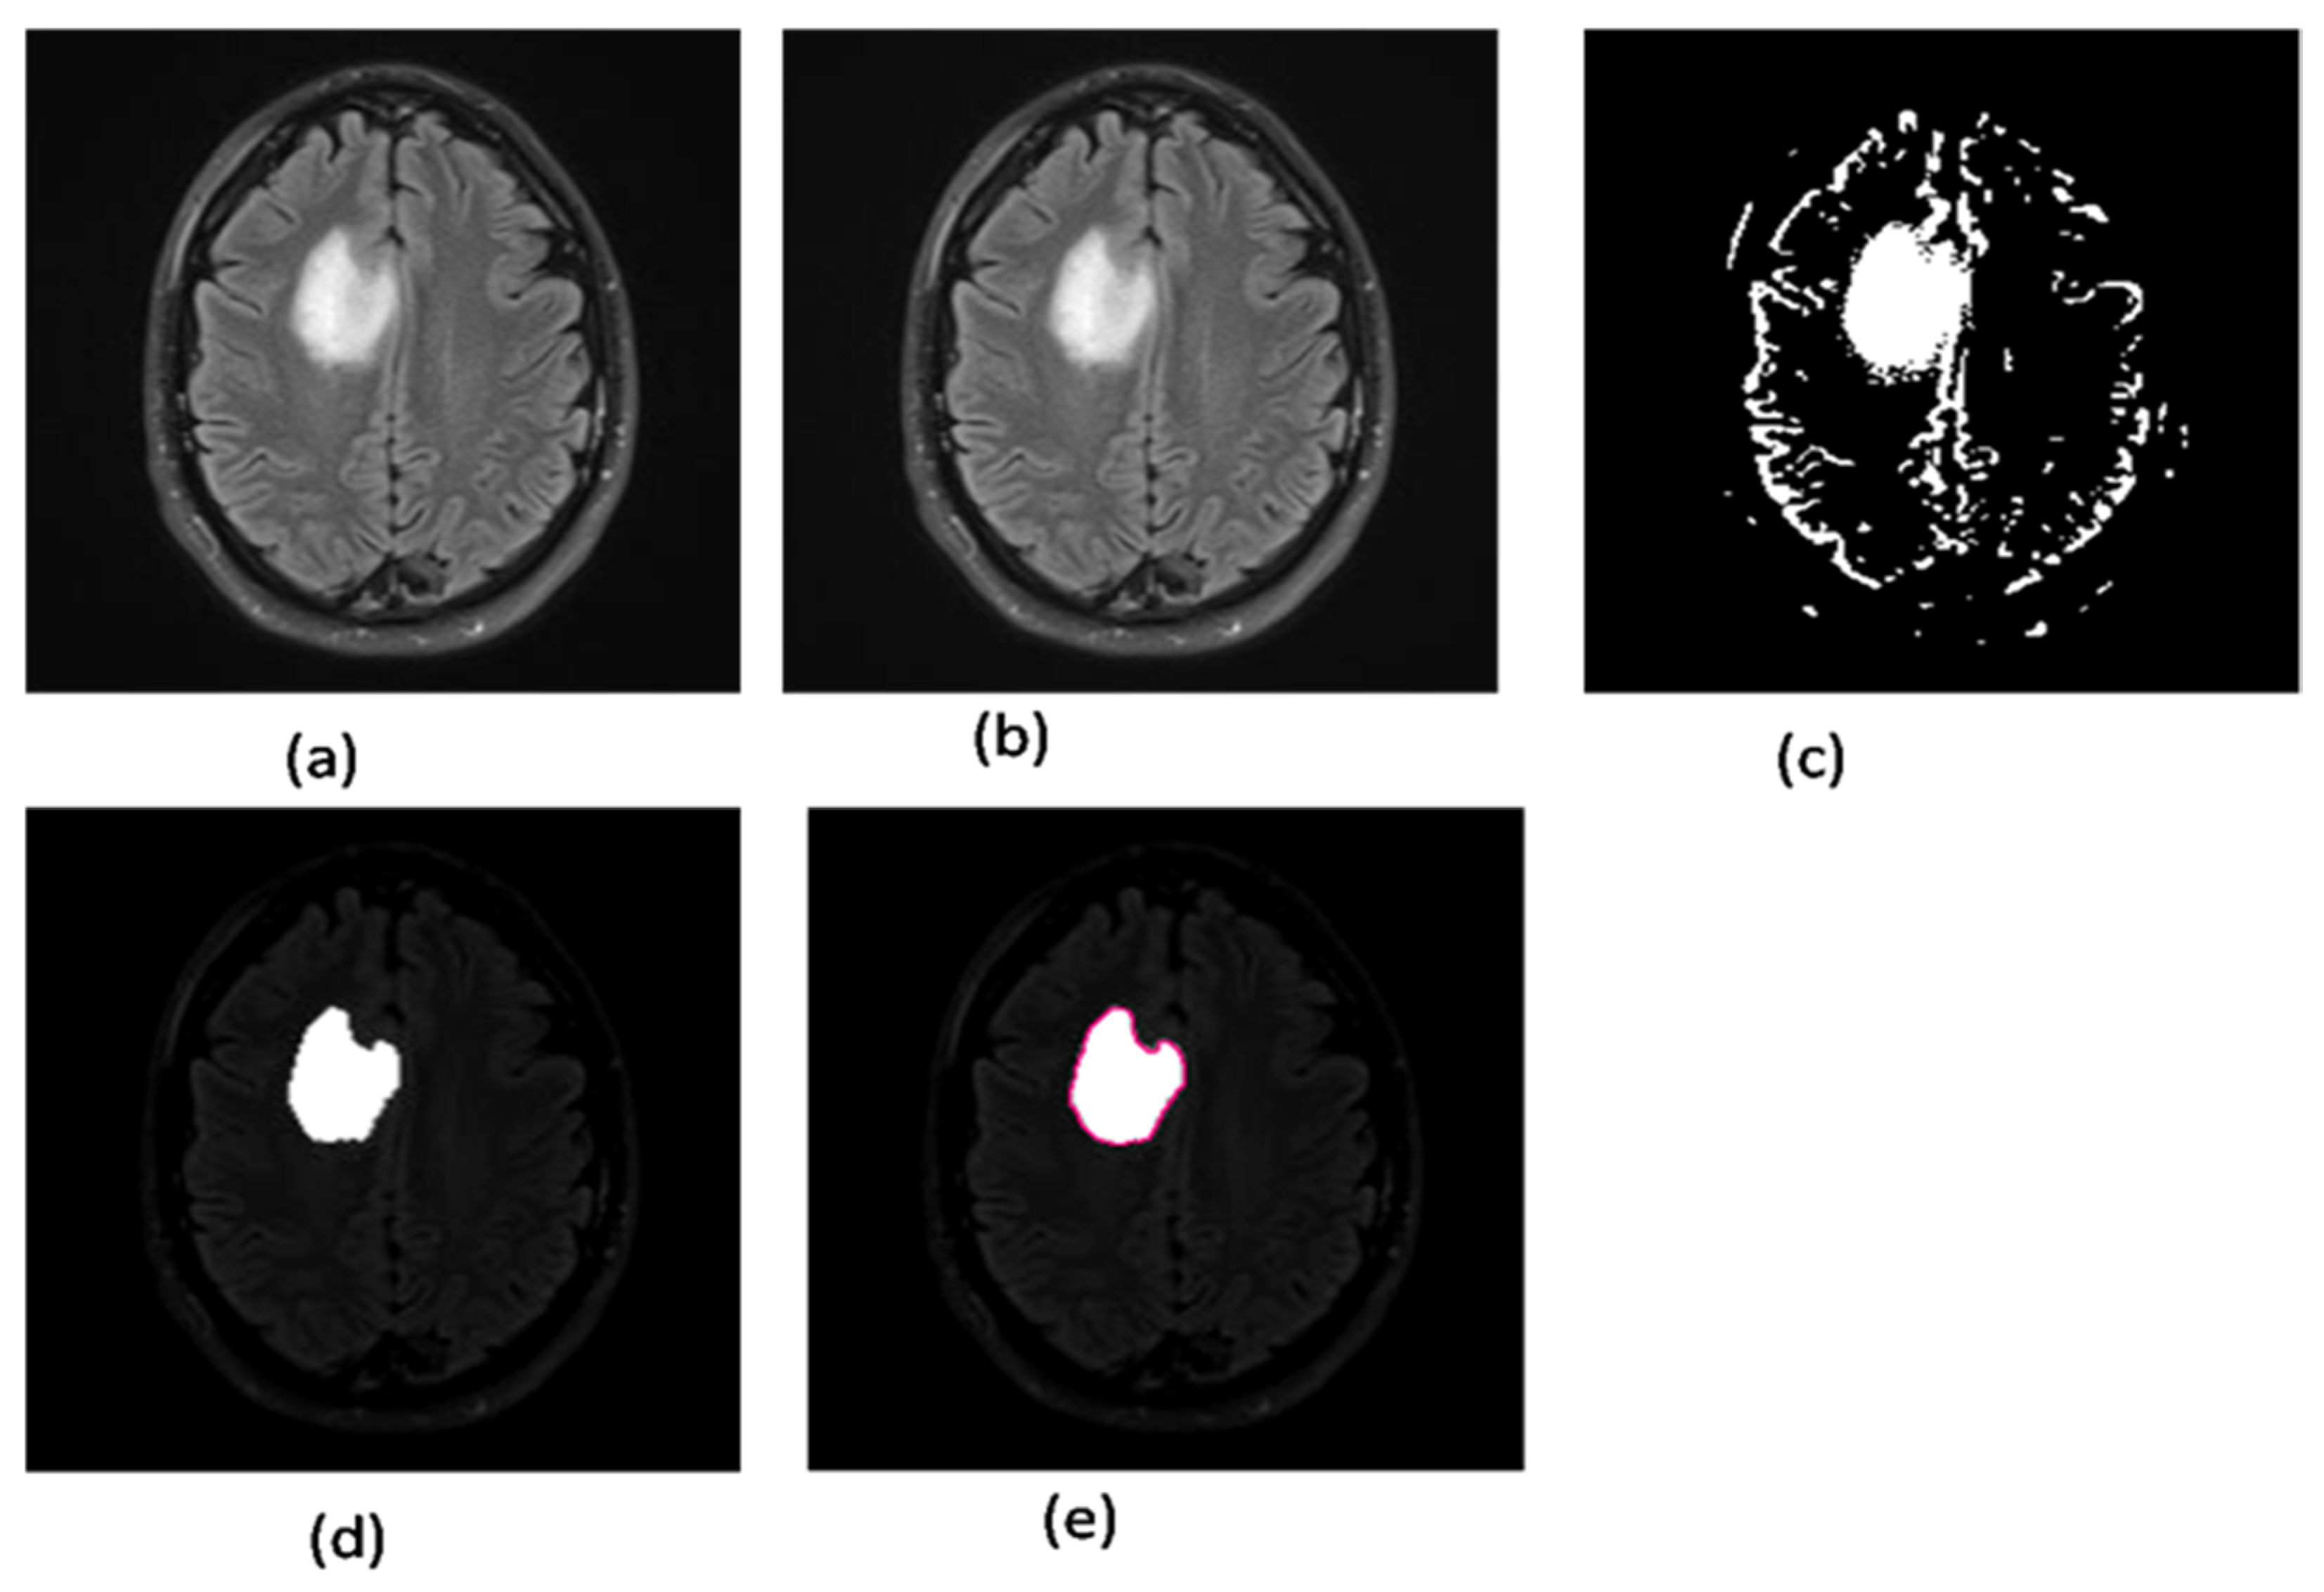

2.2.7. Area Segmentation using Watershed Algorithm

2.2.8. Region Masking and the Separation

- Strel: this command is used to create elements of morphological structure;

- Imerode: this function shrunk (eroded) the image;

- Imdilate: this function dilated the image and filled the areas after expanding.